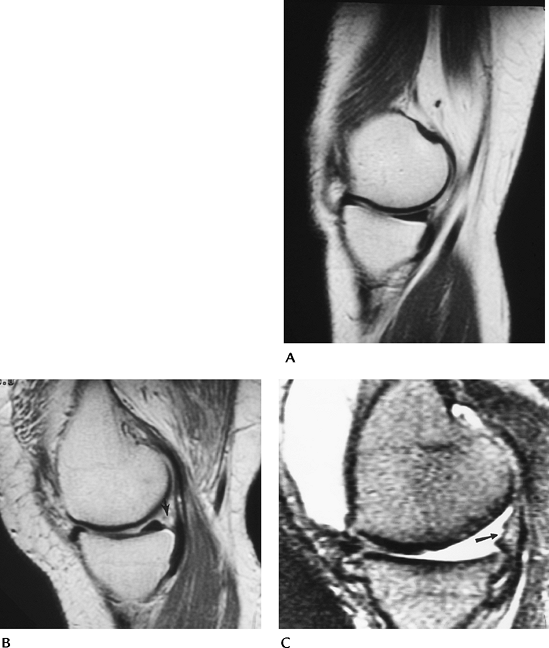

FIGURE 5-80 Popliteus muscle tear. (A) Sagittal T2-weighted image demonstrates increased signal intensity in the popliteus muscle (arrows). The PCL is hooked (arrowhead) because of an associated ACL tear. Note the joint effusion. (B)